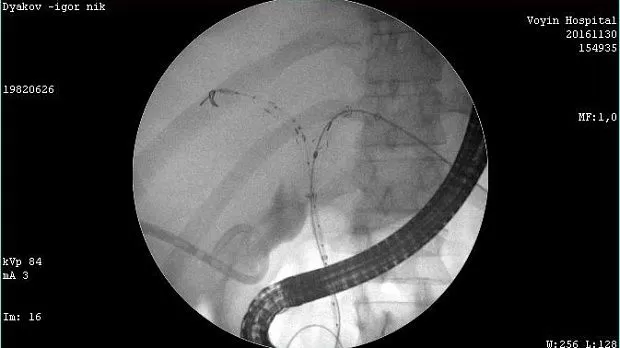

Молодой человек 33 г. Диагноз подтвержден. Стентирован пластиковыми стентами, потом самораскрывающимися. Одномоментно анте и ретроградно - с хорошим результатом. Дальше был поставлен в очередь на трансплантацию. Дальнейшая судьба не известна.